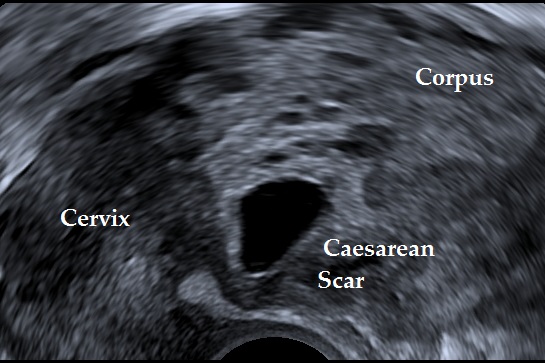

Cesarean Scar Pregnancy